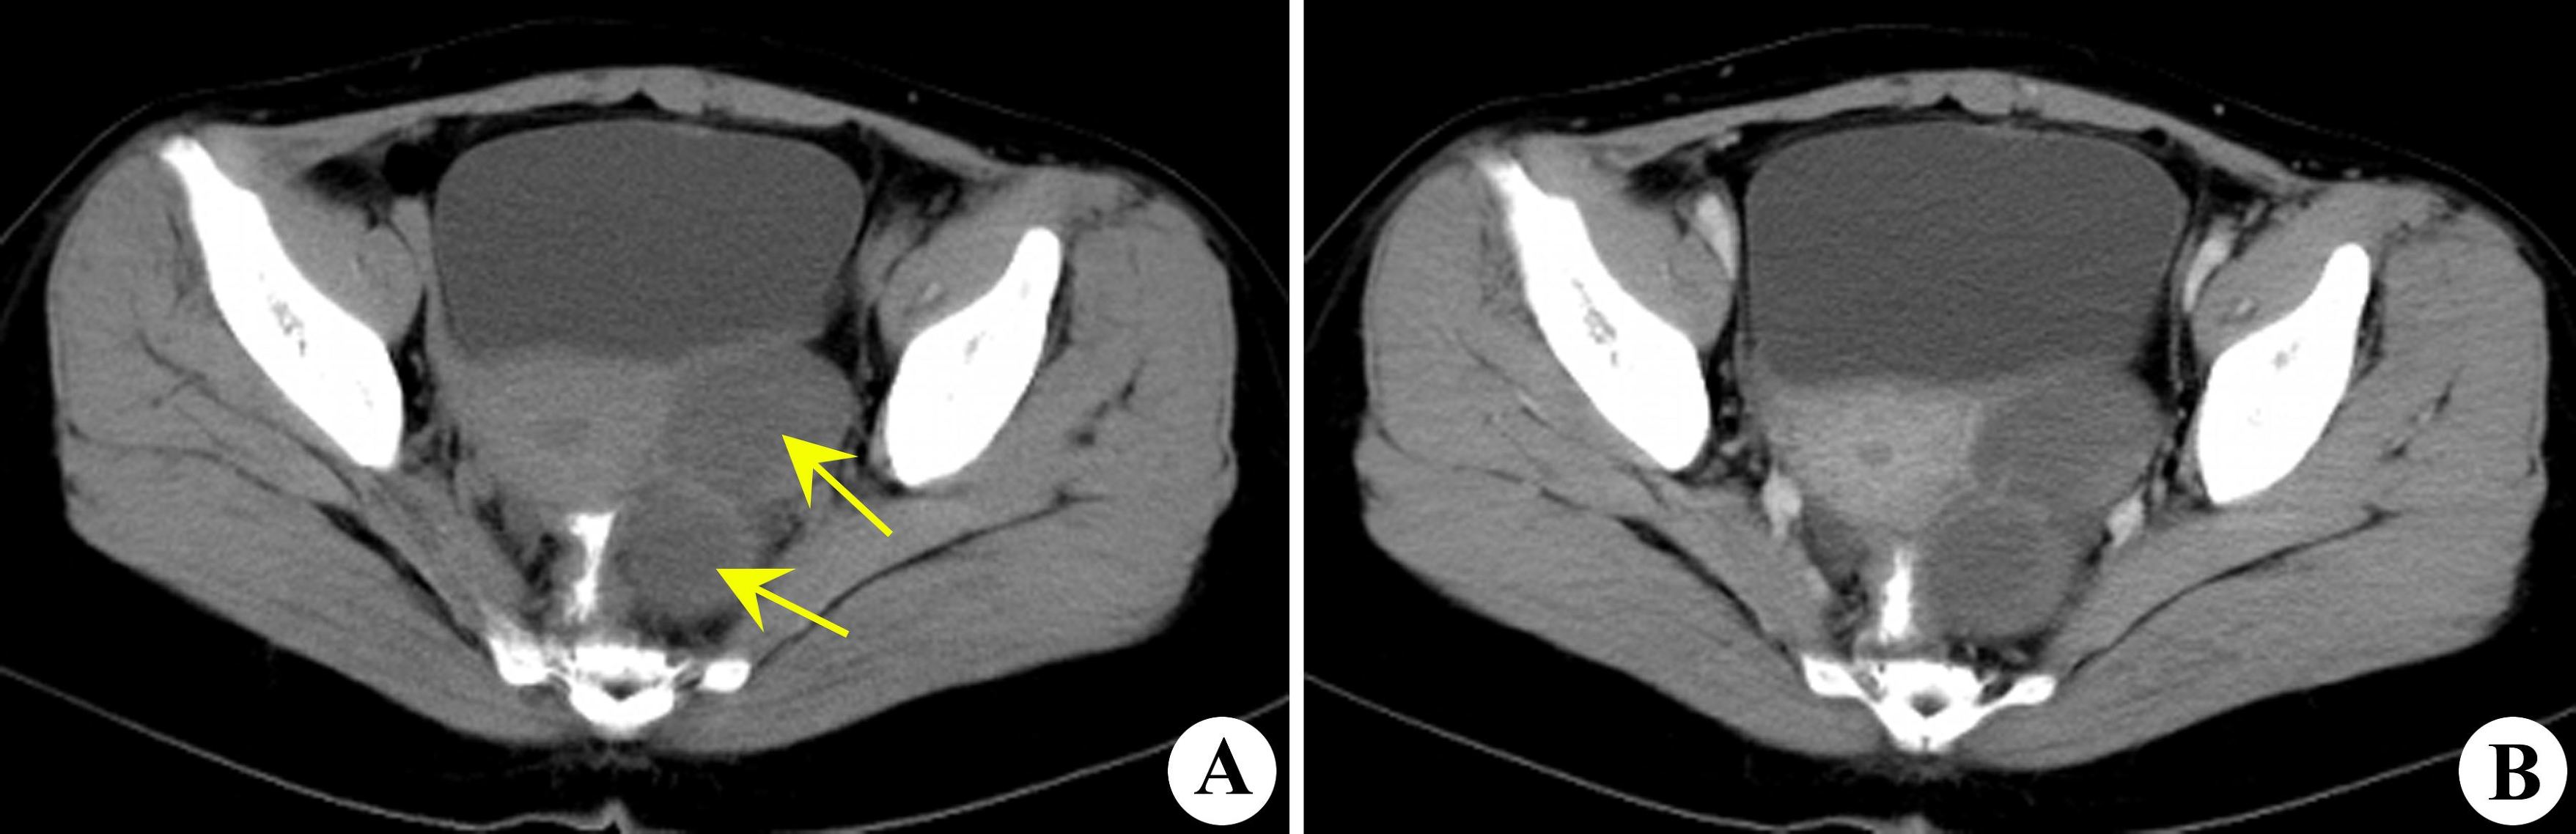

如果患者有不孕病史,并且巧克力囊肿在四公分以上,应该积极考虑手术治疗。手术的目的是去除病灶,剔出囊肿,恢复正常的解剖结构,并进行生育力的的评估,促进怀孕。